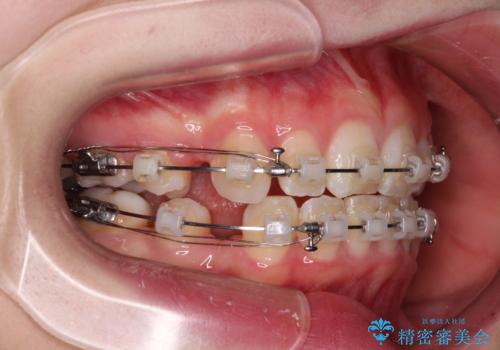

- 矯正装置

- クリアブラケット

- 治療期間

- 2年4ヶ月

- 治療回数

- 10-30回